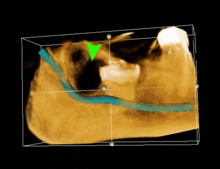

| 3D CT of an impacted wisdom tooth adjacent the inferior alveolar nerve prior to removal of wisdom tooth | |

If the tooth cannot be assessed with clinical exam alone, the diagnosis is made using either a panoramic radiograph or cone-beam CT. Where unerupted wisdom teeth still have eruption potential several predictors are used to determine the chance of the teeth becoming impacted. The ratio of space between the tooth crown length and the amount of space available, the angle of the teeth compared to the other teeth are the two most commonly used predictors, with the space ratio being the most accurate. Despite the capacity for movement into early adulthood, the likelihood that the tooth will become impacted can be predicted when the ratio of space available to the length of the crown of the tooth is under 1.[3]:141

Long-term complications can include periodontal complications such as bone loss on the second molar following wisdom teeth removal. Bone loss as a complication after wisdom teeth removal is uncommon in the young but present in 43% of those of 25 years of age or older. Initiation or worsening of temporomandibular joint problems is uncommon and unpredictable. Injury to the inferior alveolar nerve resulting in numbness or partial numbness of the lower lip and chin has reported rates that vary widely from 0.04% to 5%. The largest study is from a survey of 535 oral and maxillofacial surgeons in California, where a rate of 1:2,500 was reported. The large variation in report rates is attributed to variations in technique, the patient pool and surgeon experience. Other complications that are uncommon have been reported including persistent sinus communication, damage to adjacent teeth, lingual nerve injury, displaced teeth, osteomyelitis and jaw fracture.[19] Alveolar osteitis, post-operative infection, excessive bleeding may also be expected.[22]

Coronectomy is a procedure used when the surgeon believes that there is a high risk of inferior alveolar nerve injury. After making the incision in the mucosa and removing bone adjacent the tooth, the crown is cut and removed with no attempt at removing the roots. It is indicated when there is no disease of the dental pulp or infection around the crown of the tooth and there is a high risk of inferior alveolar nerve injury.